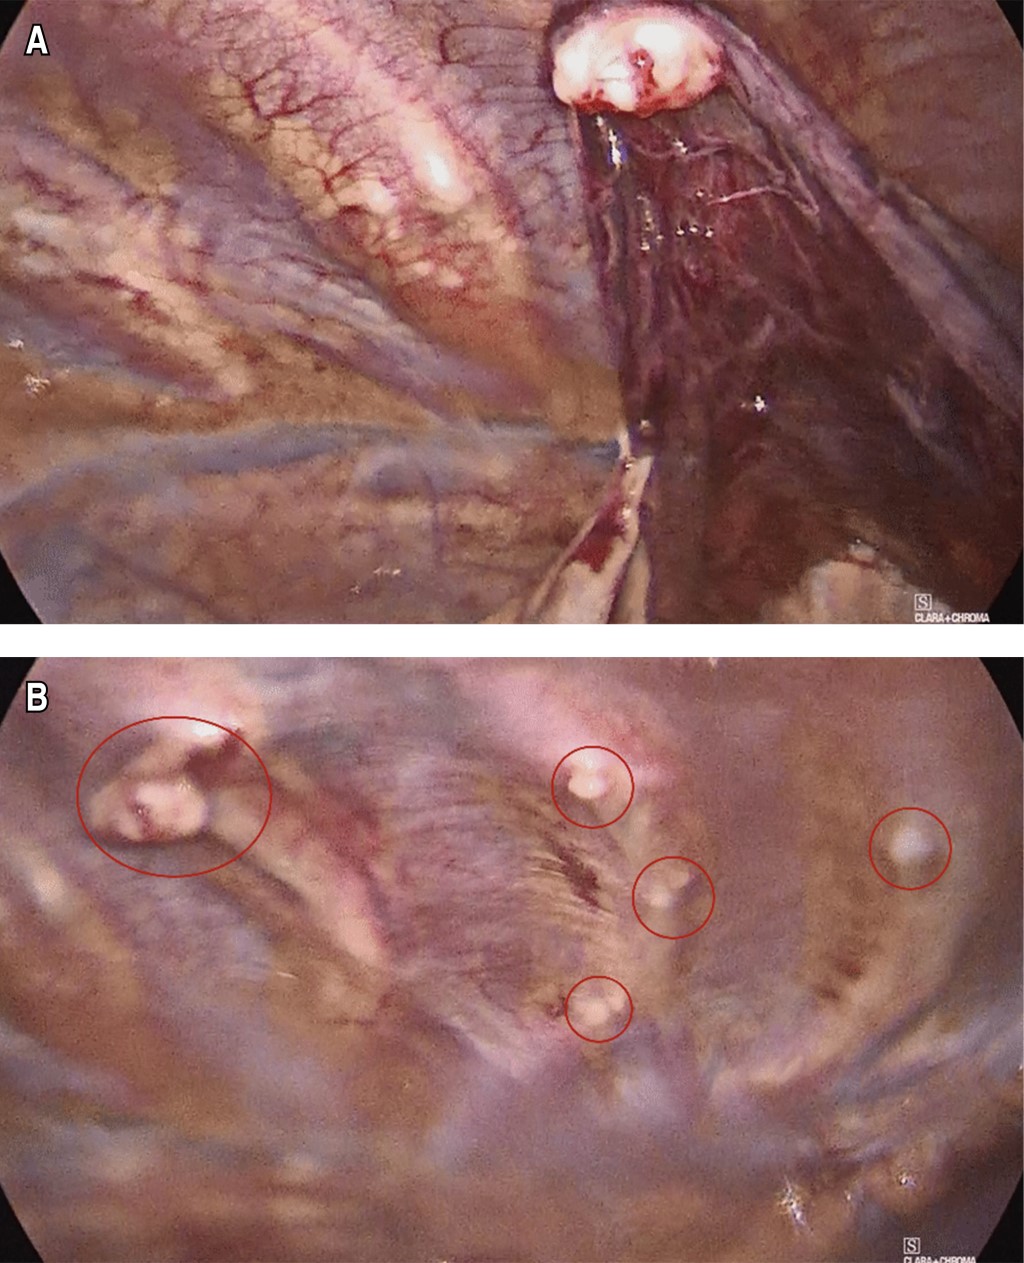

Exostosis costal como causa infrecuente de hemotórax. A propósito de un caso